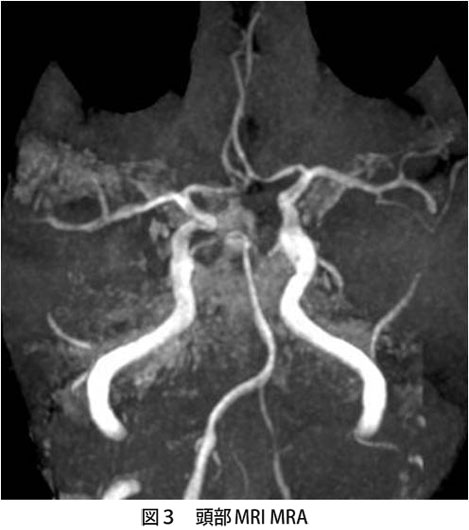

脳の動脈